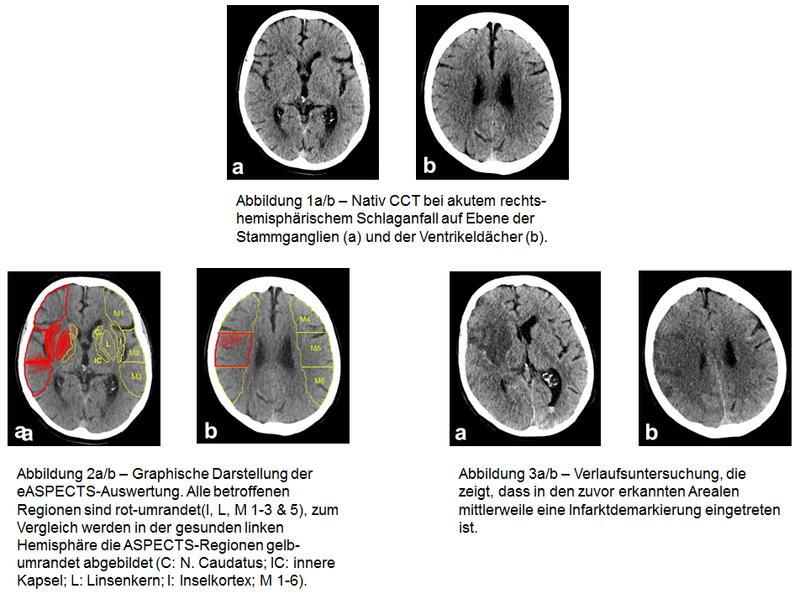

In den großen klinischen Studien erhielten vor allem solche Patienten eine Thrombektomie, deren Schlaganfall in der CT-Untersuchung einen gewissen Schweregrad nicht überschritten hatte. Dieser Schweregrad wird üblicherweise anhand eines Scores ermittelt, der „Alberta Stroke Programme Early CT Score“, kurz ASPECTS. So durfte der ASPECTS in den meisten erfolgreichen Studien (etwa ESCAPE und SWIFT-PRIME, REVASCAT) nicht schlechter als sechs oder sieben Punkte sein. Der Maximalwert beträgt zehn Punkte.

Die Bestimmung des ASPECTS ist Standard bei Patienten, die wegen eines frischen Schlaganfalls eine CT-Untersuchung erhalten. „Die manuelle Ermittlung dieses Scores erfordert aber ein hohes Maß an Erfahrung und ist anfällig für Fehleinschätzungen“, betont Herweh. Abhilfe schaffen könnte eine softwarebasierte Ermittlung des ASPECTS. „Sie ist objektiver und kann die Prognose der Patienten möglicherweise besser abschätzen als Radiologen dies können.“

Mit eASPECTS von Brainomix existiert seit einiger Zeit eine solche Software, die zunehmend ihren Wert in klinischen Studien unter Beweis stellt. Dr. Herweh berichtet über die aktuellsten Daten beim 98. Deutschen Röntgenkongress / 8. Gemeinsamen Kongress der DRG und ÖRG (24.-27. Mai 2017, Leipzig). In einer ersten Validierungsstudie mit 34 Patienten konnte gezeigt werden, dass die softwarebasierte Auswertung der CT-Bilder der Auswertung durch Radiologen mit wenig Training überlegen und der durch Experten gleichwertig ist. Eine weitere, britische Studie hat bei 132 Patienten bestätigt, dass die Software im Vergleich zu Neuroradiologen nicht unterlegen ist.

Die Software funktioniert also technisch gesehen. Aus klinischer Sicht ist die eigentlich interessante Frage aber, ob sie geeignet ist, besser als oder zumindest genauso gut wie Experten vorherzusagen, welche Patienten einen schlechten klinischen Verlauf haben. Dazu haben Herweh und Kollegen jetzt eine dritte Studie durchgeführt. Bei 212 Patienten mit frischem Schlaganfall wurde rückblickend der ASPECTS durch drei Experten und durch die Software ermittelt. Das Ergebnis wurde dann mit dem tatsächlichen klinischen Verlauf der Patienten korreliert.